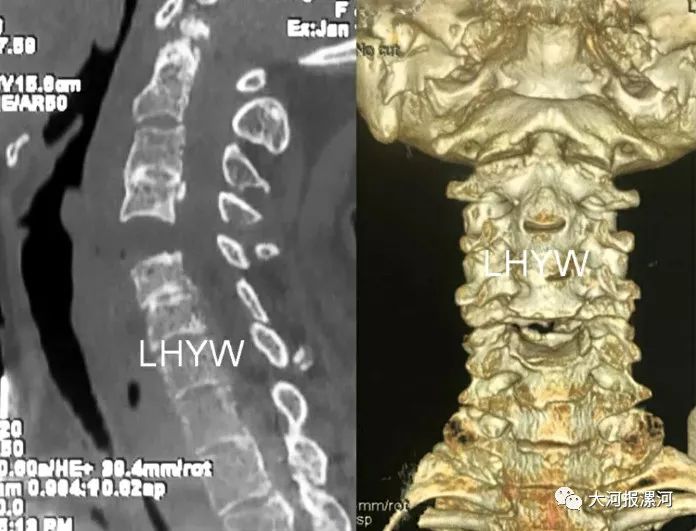

查看患者CT后,发现患者是罕见的颈椎骨折后分离移位,并合并肋骨骨折,血气胸,情况十分凶险,稍有不慎即可发生呼吸功能衰竭或高位截瘫的风险。患者无亲属陪同,周鹏保护患者的颈椎,并指导急救中心医护人员共同搬运护送患者到住院部12楼脊柱外科病房,积极进行紧急处理,稳定生命体征。

关节脊柱病区副主任、脊柱外科副主任李玉伟查房亲自查看患者,详细查体询问病情后认为患者患有严重的强直性脊柱炎,这次的车祸挥鞭样损伤导致颈椎横断骨折,大多患者当场去世。

但该名患者万幸的是脊髓未明显受压,损伤节段也巧妙的避开了危险区域。李玉伟叮嘱科室团队,必须时刻注意患者的颈椎制动,进行术前检查时候的体位搬运需要格外小心,并指派科室李凡医师全程陪送患者进行搬运时的颈椎守护工作,因为稍有不慎患者即刻完全瘫痪,并难以恢复。